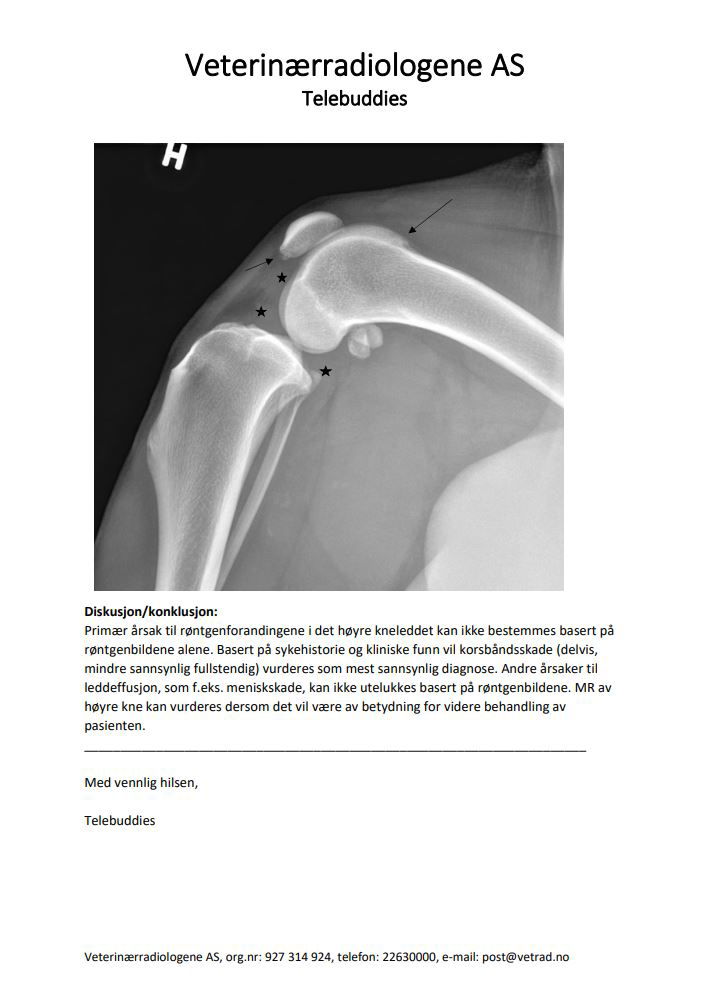

Signalement: Golden retriever, hannhund, 9år. Anamnese: Kom løpende ute og bommet på en trapp opp til en veranda. Hylte til og var akutt 5/5 grader halt på høyre bakbein. Redusert til 3-4/5 ila 30 min. Fått NSAIDs og holdt i ro. Kliniske funn: 2/5 grader halt i skritt, får NSAIDs. Mild til moderat fylning i høyre kneledd. Mild positiv “tibial thrust” på flektert kne, får ikke frem på ekstendert kne.